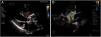

A los pocos meses, la paciente presentó clínica de insuficiencia cardiaca progresiva hasta ingresar en situación de anasarca. En la ecografía transtorácica (fig. 1 A y vídeo 1 del material adicional en anexo) y transesofágica (figura 1 B y vídeo 2 del material adicional en anexo) se observa fuga paraprotésica anterior (flecha) y amplio seudoaneurisma (asterisco) en la región posterior de la raíz aórtica (Ao), con flujo diastólico en su interior. También se observa la comunicación del seudoaneurisma, que presenta flujo de entrada supravalvular en raíz aórtica y de salida a ventrículo izquierdo, hallazgos que se comprueban posteriormente en la tomografía computarizada multidetector de 64 cortes (fig. 2 A y B) (fig. 3). Se realizó reparación quirúrgica con implante de homoinjerto criopreservado de raíz aórtica con buena evolución posterior.